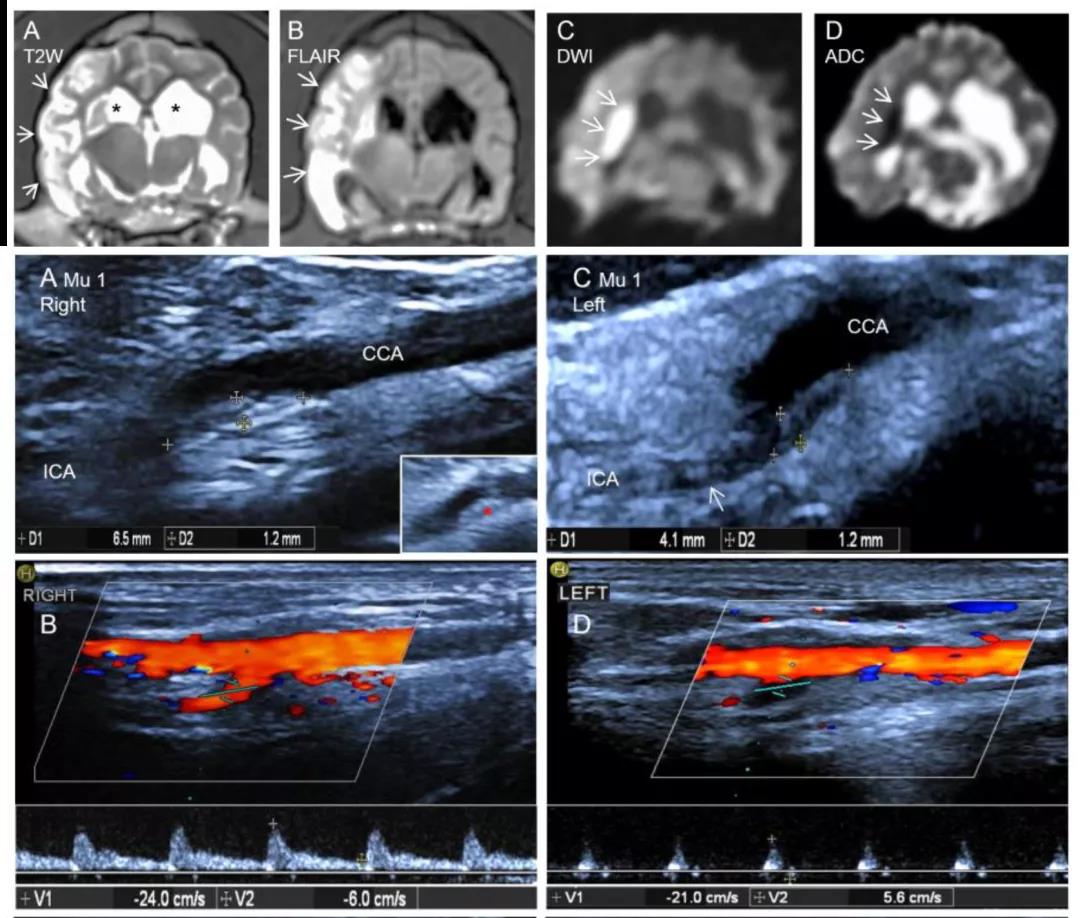

通过进一步对其进行磁共振 (MRI) 以及超声检测分析,显示ApoE基因编辑敲除犬脑部多处出现由于动脉粥样硬化导致的明显缺血性梗塞,颈内动脉出现明显斑块以及血管狭窄现象。

ApoE基因编辑敲除犬出现脑部明显缺血性梗塞,颈内动脉斑块以及血管狭窄现象(1)

ApoE基因编辑敲除犬出现脑部明显缺血性梗塞,颈内动脉斑块以及血管狭窄现象(2)